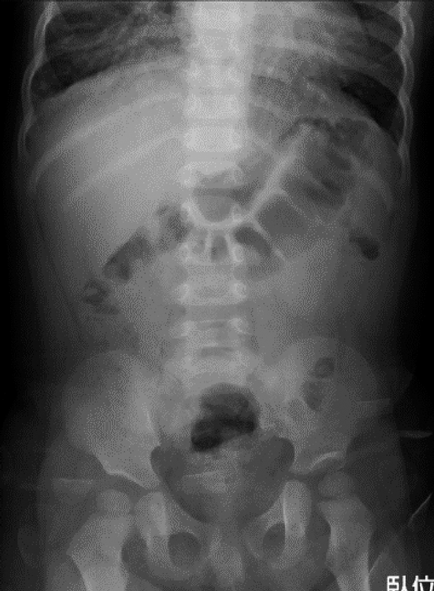

A 1-year-old Japanese girl with a three-hour history of diaphoresis and emesis, was brought to our emergency room (ER) by her mother. She was diagnosed with acute gastroenteritis (Fig. 1) and was discharged back to her home. Five hours later, the patient had recurrent emesis, which progressed to apnea. The child was driven by her mother back to the same ER. Upon arrival, the child was in cardiopulmonary arrest. Her initial electrocardiogram finding revealed asystole. Unfortunately, despite an hour of cardiopulmonary resuscitation, the patient died.

Fig. 1 Abdominal radiograph (5 hours before death)